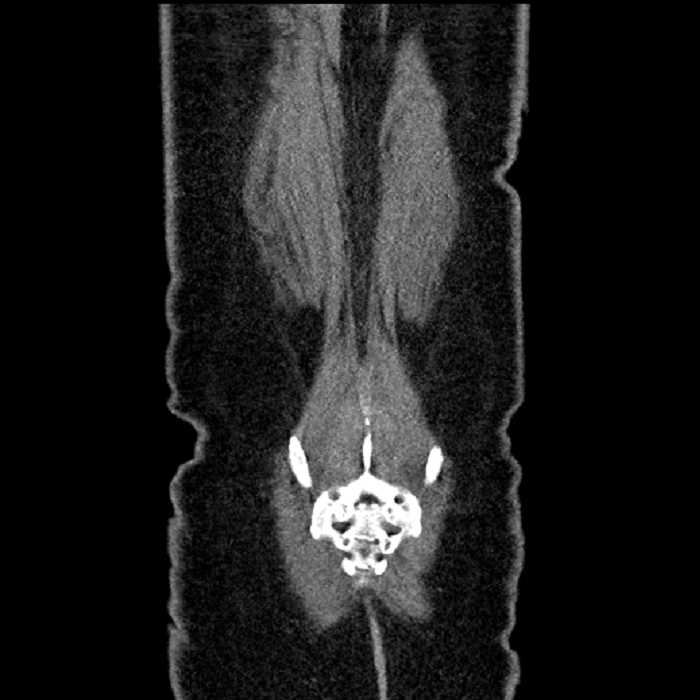

• Mild mural thickening of a segment of the sigmoid colon with adjacent fat stranding and a 1.5 cm fluid and gas collection along the tip of an inflamed diverticulum

• Loss of the normal fat plane between this collection and adjacent loops of small bowel, which demonstrate mural thickening

Additionally, loss of the normal fat plane between the peridiverticular collection and adjacent thickened loops of small bowel raises the potential for an enterocolonic fistula.

Hepatic abscess showing the double target sign with low density internally surrounded by a thin inner enhancing rim (red arrow) and ill-defined outer low density rim (yellow arrow). Blue arrow indicates an internal septation. Red arrows: additional smaller subcapsular abscesses. Red arrow: focal contained perforation associated with diverticulitis.